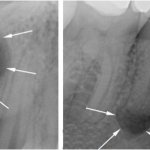

Это современный метод, который заключается в бережной шлифовке и полировке зубов, когда врач аккуратно снимает тончайший слой эмали с помощью особой смеси с абразивными частицами. Толщина снимаемого слоя обычно не превышает 25-70 мкм, что дает возможность предупредить чрезмерное истончение эмали и, соответственно, развитие гиперестезии, то есть ее высокой чувствительности. В особо сложных случаях снимают до 200 мкм1. Как зубы выглядят до и после процедуры, можно оценить по фото ниже.

На фото показаны зубы до и после процедуры микроабразии